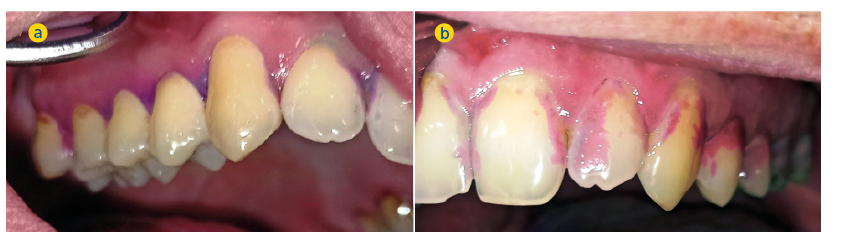

Deutlich mehr approximaler und vestibulärer Biofilm auf der paretischen Mundhälfte (2. Quadrant, Abb. 2b) als auf der nicht paretischen Seite

(1. Quadrant, Abb. 2a)

Die Plaque-Kontamination war in Bezug auf den API auf der paretischen Seite um 10,9 % (p = 0,004) höher als auf der nicht paretischen Seite. Ebenso wiesen die vestibulären Zahnoberflächen der paretischen Seite mehr Biofilm auf als die der nicht paretischen Seite (p = 0,002; s. Tab. 3, Abb. 2a und b). Dabei war der Unterschied bei den männlichen Patienten (0,8 vs. 0,5; p = 0,001) größer als bei den weiblichen Patienten (0,6 vs. 0,4; p = 0,002). Außerdem wurde bei Patienten mit rechtsseitiger Fazialisparese ein größerer Seitenunterschied (0,7 vs. 0,5; p < 0,001) dokumentiert als bei Patienten mit linksseitiger Fazialisparese (0,5 vs. 0,4; p = 0,043). Ursächlich erschien die Händigkeit der Patienten. Während bei Patienten mit linksseitiger Fazialisparese die Erkrankung auf der für Rechtshänder besser zu reinigenden Mundhälfte vorlag, waren rechtshändige Patienten mit rechtsseitiger Fazialisparese einer doppelten Belastung ausgesetzt (18). Die Gingivablutung nach Sondierung war auf der paretischen Seite ebenfalls signifikant höher als auf der nicht paretischen Seite (s. Tab. 3). Das spiegelte sich sowohl bei den Werten des SBI (s. Tab. 3, Abb. 3) als auch bei den Werten des PBI (s. Tab. 3, Abb. 4a und b) wider. Die Sondierungstiefen waren auf der paretischen Seite im Vergleich zur nicht paretischen Seite tiefer und der Attachmentverlust war höher. Dabei konnte jedoch kein signifikanter Unterschied nachgewiesen werden. Der mittlere PSI erreichte auf der paretischen Seite signifikant höhere Werte als auf der nicht paretischen Seite